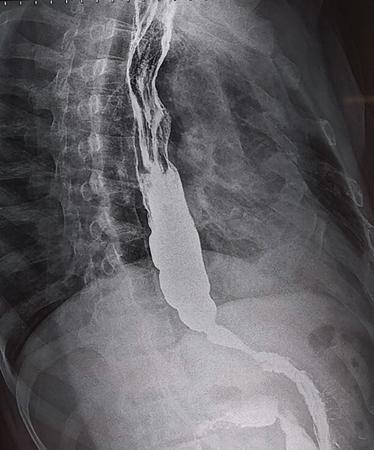

A 60-year-old male with history of chronic alcohol consumption and chronic weight loss and pain epigastrium presented to Radiology for USG. A finding on USG called for a barium meal and follow-through for academic purpose.

Key findings

Barium meal and follow-through spot image revealed widening of C loop of duodenum along with extrinsic compression on the antrum posteroinferiorly giving rise to classical ‘antrum pad’ sign. There was, however, no obvious mucosal irregularity seen. There is evidence of contrast hold-up.

Analysis and interpretation

The image showcases two classical signs in GI radiology which are the ‘widening of C loop of duodenum’ and the ‘antral pad sign’. Both the signs are typically described in masses of head of pancreas. A comment on the mucosal lining (regular/irregular) may give a pointer towards the mass being malignant. However, this is a nonspecific sign giving indication of a mass effect and has a variety of differentials. The final diagnosis is reached with the help of cross-sectional imaging and/or endoscopy/biopsy. CECT abdomen in this case confirmed it to be a case of carcinoma pancreas (Fig. 7.4.6.1).

Image

Fig. 7.4.6.1 CECT showing a mass in the head of pancreas.

Pseudocyst of pancreas

• a) Two classical signs described above.

• b) Smooth indentation and smooth mucosa.

• c) USG/CT will show the cystic nature.

Fig. 7.4.6.3 CECT abdomen showing a large pseudocyst.